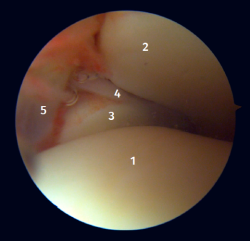

Visión artroscópica posterior

Desde el abordaje posterolateral identificaremos el maléolo peroneo y, desde aquí, visualizaremos las fibras intraarticulares del LTPP, que se dirigen de forma oblicua insertándose en la porción distal de la tibia. También veremos el engrosamiento distal del LTPP (ligamento transverso) en continuidad con el labio posterior de la tibia distal (Figura 4).

Figura 3. Visión artroscópica anterolateral de un tobillo derecho al introducirnos en la tibioastragalina. 1: cúpula astragalina; 2: cara articular de la tibia; 3: peroné; 4: articulación tibioperonea distal; 5: fibras distales del ligamento tibioperoneo anterior.